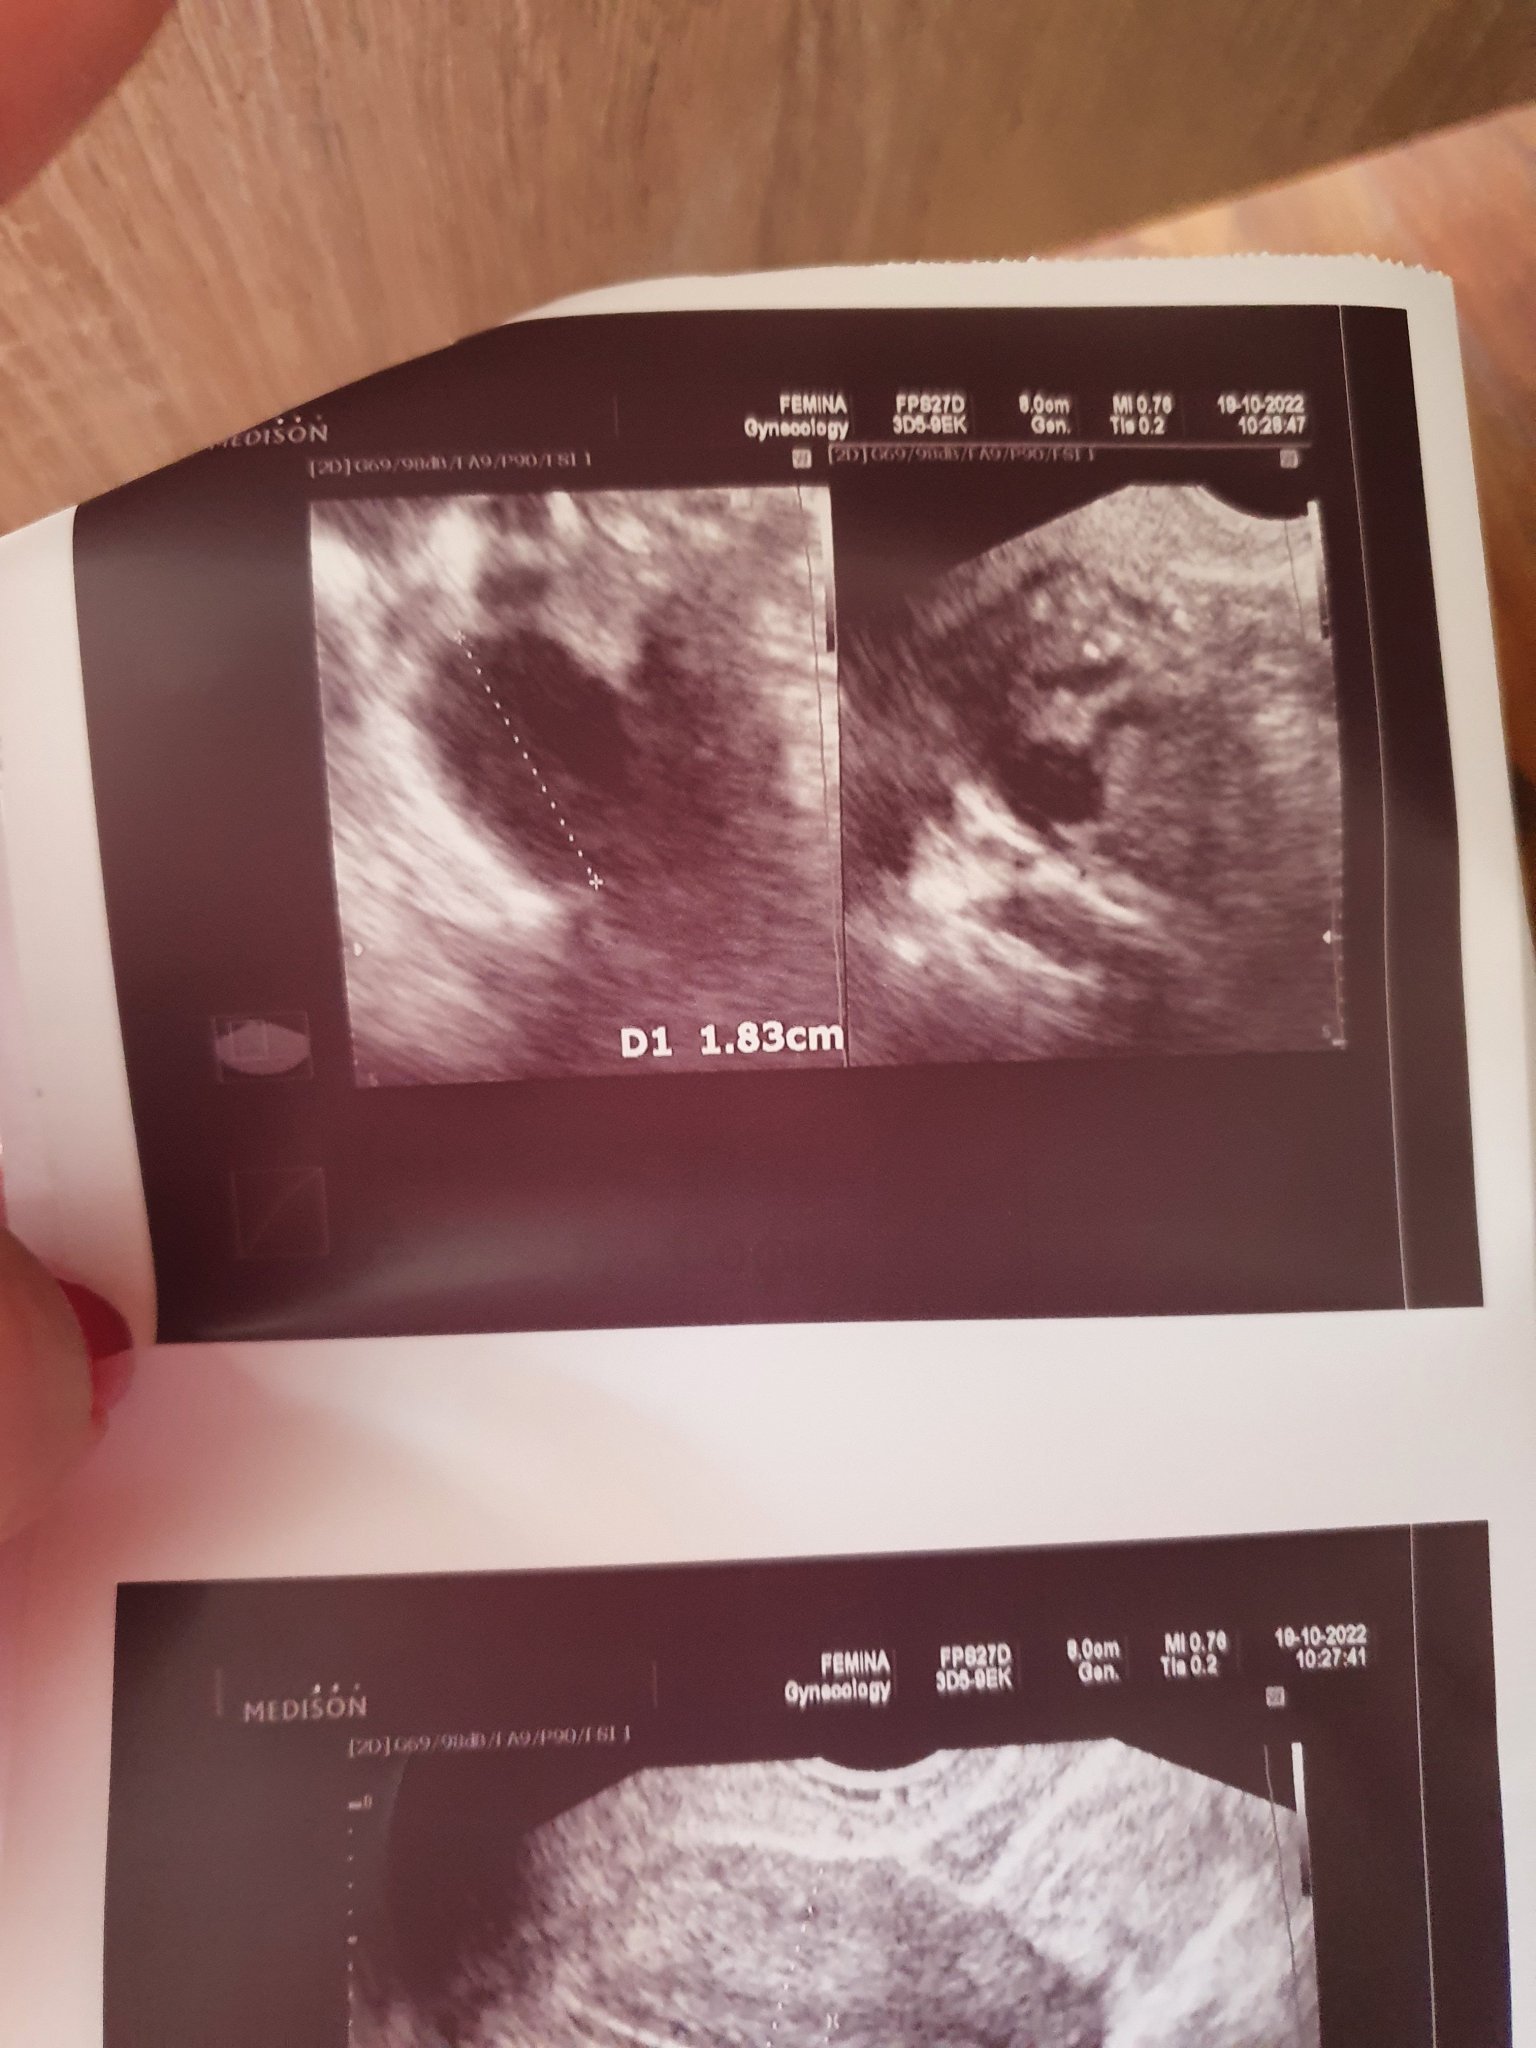

Здравейте, сряда (10 ден от цикъл) бях на гинекологичен преглед. Така и така бях преди овулация, гинеколожката като ми видя десния яйчник ми каза направо "Ще ти кажа кога точно да правите опити - петък", сиреч днес, 12 ден от цикъла.

Ето снимката, тя се водеше от размера 1.8см и ми каза ПЕТЪК задължително.

Да, обаче аз вчера и дне си правя тестове за ову и са все с бледи черти, т.е -.

Ще прикача снимката и питам - аз аджеба да вярвам ли на лекарката или на тестовете и да изчакам още малко до плътна черта...